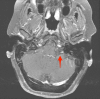

Both lipomas and dermoid cysts of the cerebellopontine angle are rare tumors. These tumors differ in their embryological origin but share similar features on imaging. Both of these congenital lesions can be found in the cerebellopontine angle (CPA), and symptomatic clinical presentation is dictated by the location of the lesion. This paper demonstrates a unique case in which a CPA lipoma was misidentified as a dermoid cyst, leading to surgical intervention. Further, the paper provides a literature review of CPA lipomas and dermoid cysts to aid readers in further differentiating between these two unique tumors.